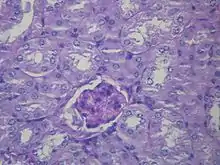

研究认为,肝衰竭會改变肠道的血液循环、肾血流量和肾的血管紧张度。因此,肝肾综合征患者的肾衰竭主要是導因於血流动力学的变化,而非肾组织的直接破坏。肝肾综合征患者的肾脏无论在巨觀上或微觀下的病理型態都是正常的,甚至若将之置于健康的环境中(如把他们移植给一个有着正常肝脏的患者),它們仍可正常发挥功能。临床上,肝肾综合征的诊断需對疑似肝肾综合征的患者進行实验室生化指标检查。肝肾综合征可分為兩種類型:1型以快速的肾功能减退为主要表现;2型则表现为腹水的产生,且無法以常规剂量的利尿剂控制。

许多其他肾脏疾病与肝脏疾病具有相关性,因此在诊断肝肾综合征时必須予以排除。肾前性肾衰竭的肾脏并未收到损伤,与肝肾综合征类似,都是由于肾血流灌注不足引起,且兩者的尿钠含量都很低;而与肝肾综合征不同的是,肾前性肾衰通常对补液疗法有反应,會使得血清肌酸酐下降以及尿钠升高[3]。急性肾小管坏死(ATN)是各种原因造成的肾小管的损伤,肝硬化患者可能在治疗过程中使用了肾毒性药物或因為低血压而造成ATN。由于小管的损坏,肾脏无法再吸收原尿中的钠,导致尿纳比肝肾综合征高出很多,以此可鉴别肝肾综合征与ATN[5]。ATN患者在尿沉渣镜检中還能发现透明管型和棕色混濁管型,而肝肾综合征的尿沉渣镜检中则难以见到细胞管型或其他细胞成分,因为肝肾综合征患者的肾实质并未受损[3]。一些病毒性肝炎(如乙型肝炎和丙型肝炎)可以导致肾小球炎症,从而造成肾功能不全[10][11]。其他可以导致肝脏疾病患者发生肾衰的原因還有药物毒性(如庆大霉素)和造影剂肾病(影像诊断時静脉注射造影剂所引起的肾功能衰竭)[3]。